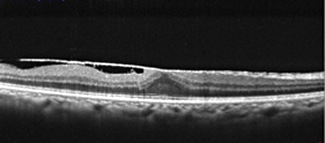

黄斑の上(表現によっては前)に膜が貼ってきて、網膜にしわが寄ったり盛り上がって形態以上をきたした状態が黄斑上膜(網膜前膜)です。